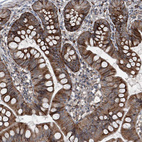

Immunohistochemical staining of human cerebral cortex shows strong cytoplasmic positivity in neurons.